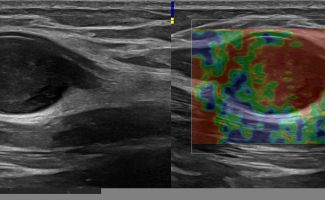

- Focal Lesions (tumors, neuromas)